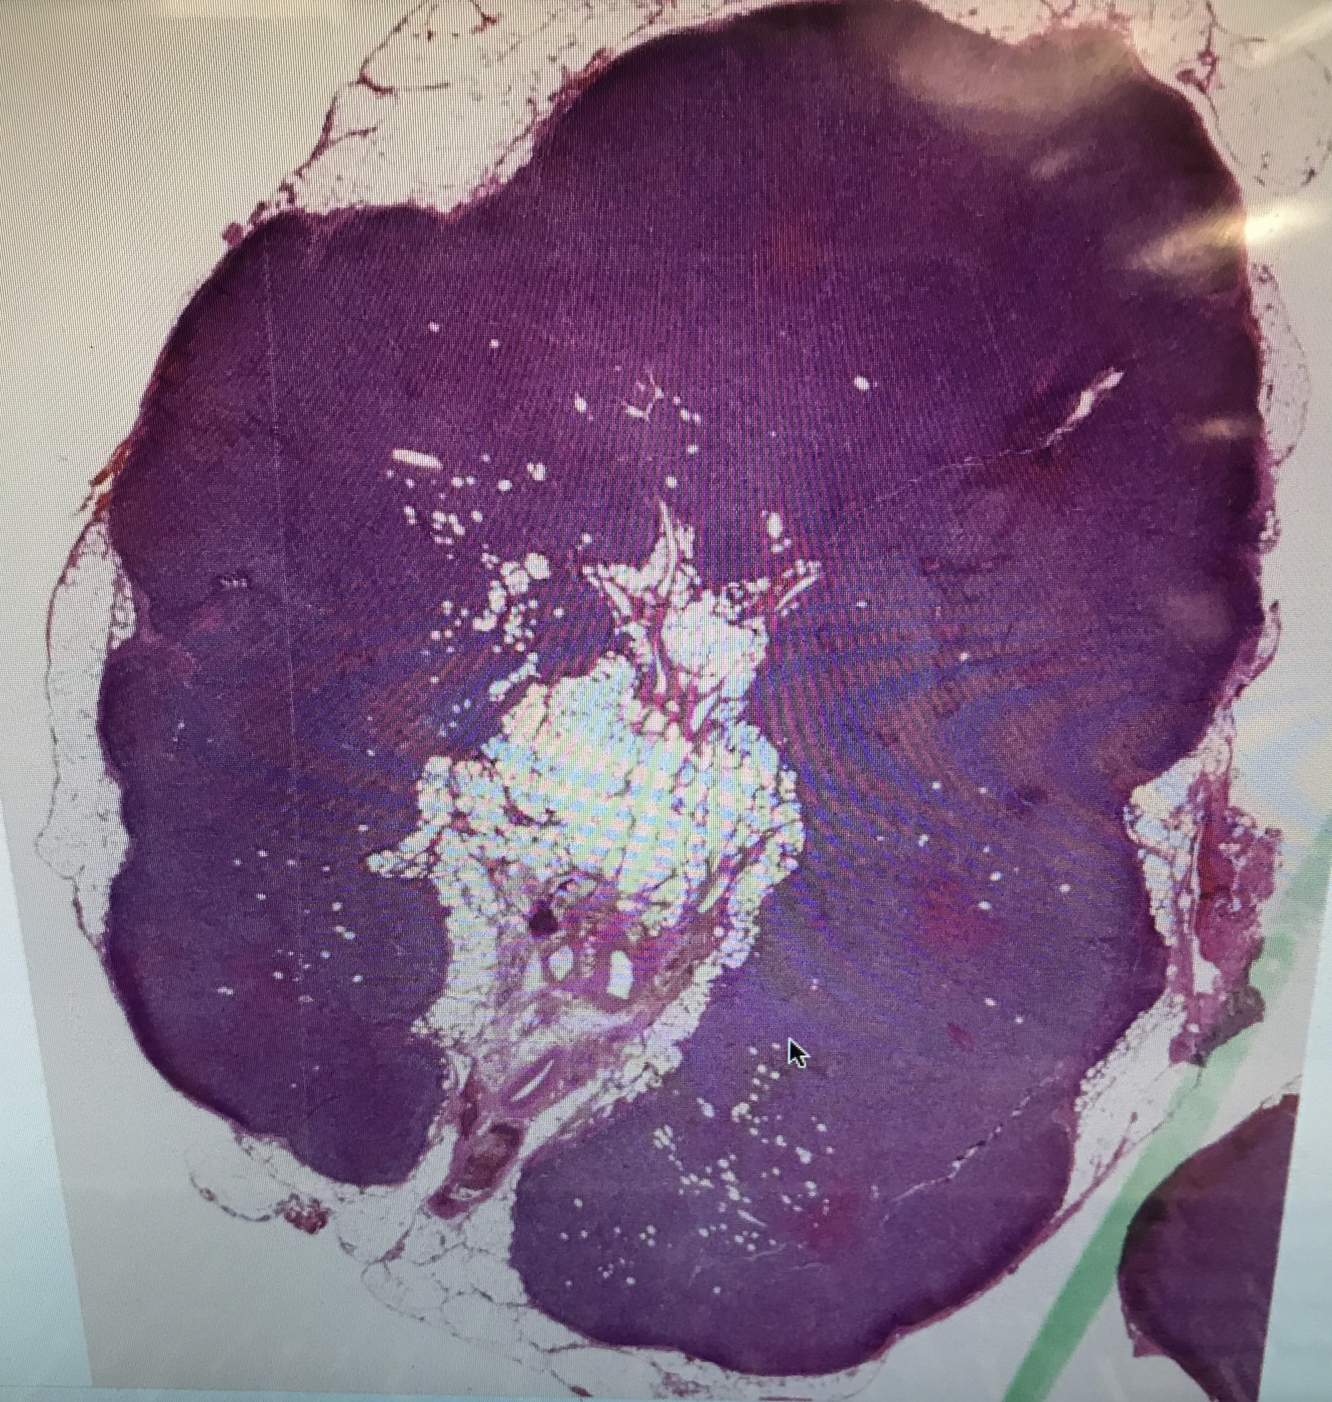

What are two major differentials to consider if you saw this biopsy image?

What is a common treatment plan for follicular lymphoma?

Describe follicular lymphoma; what is its prevalence?

What is the genetic variation that common causes follicular lymphoma?

Most characterized by t(14;18)

What is the disease progression of follicular lymphoma?

What does this image show?